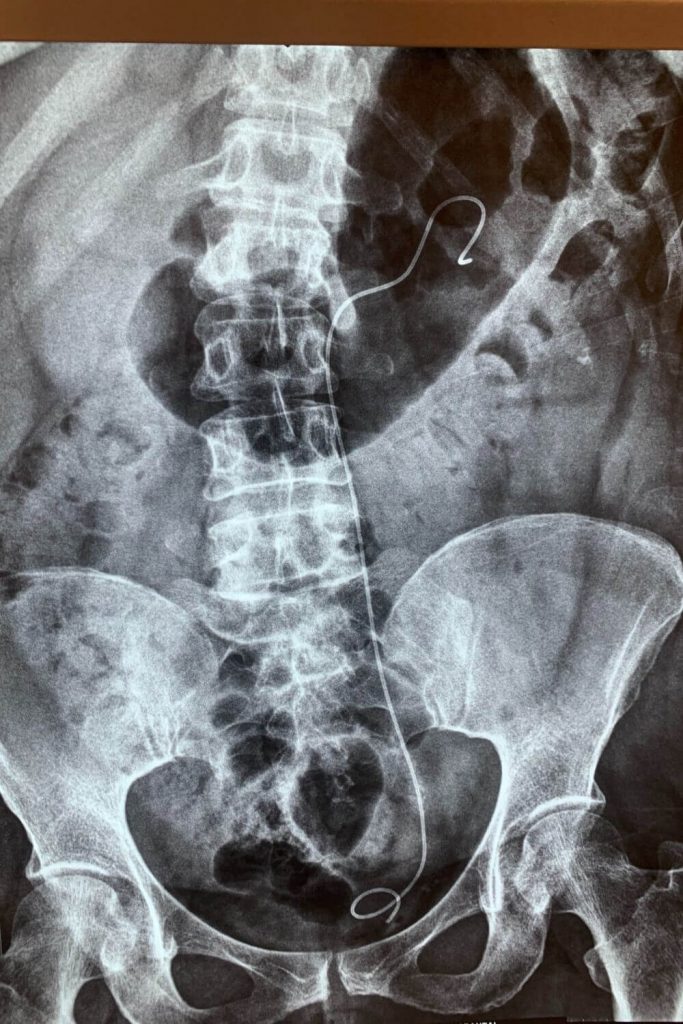

Μετά την κλινική εξέταση ακολούθησε Αξονική τομογραφία η οποία έδειξε λιθίαση του κάτω τριτημορίου (ΑΡ) ουρητήρα με ουρητηρουδρονεφρωση.

Κατόπιν έγινε ουρητηροσκόπηση και ενδοσκοπική λιθοτριψία με Laser.

Η ασθενής έλαβε εξιτήριο την ίδια ημέρα ενώ το stent αφαιρέθηκε σε 2 εβδομάδες.